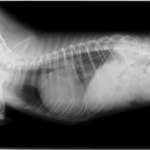

症例:【マルチーズMix 1歳齢 メス】

A:胸部レントゲン写真 正面像

B:胸部レントゲン写真 側面像

C:超音波画像 肺動脈領域の異常血流

D:左心系の拡張による二次的僧帽弁逆流

左側胸壁よりLevine 4/6の連続性心雑音が聴取された。胸部レントゲン検査において心拡大が認められ、超音波検査においても肺動脈領域に連続的な異常血流が観察された。大学病院を紹介受診され、手術が行われた。現在はACE阻害薬のみの内服で補助的治療を行っている。